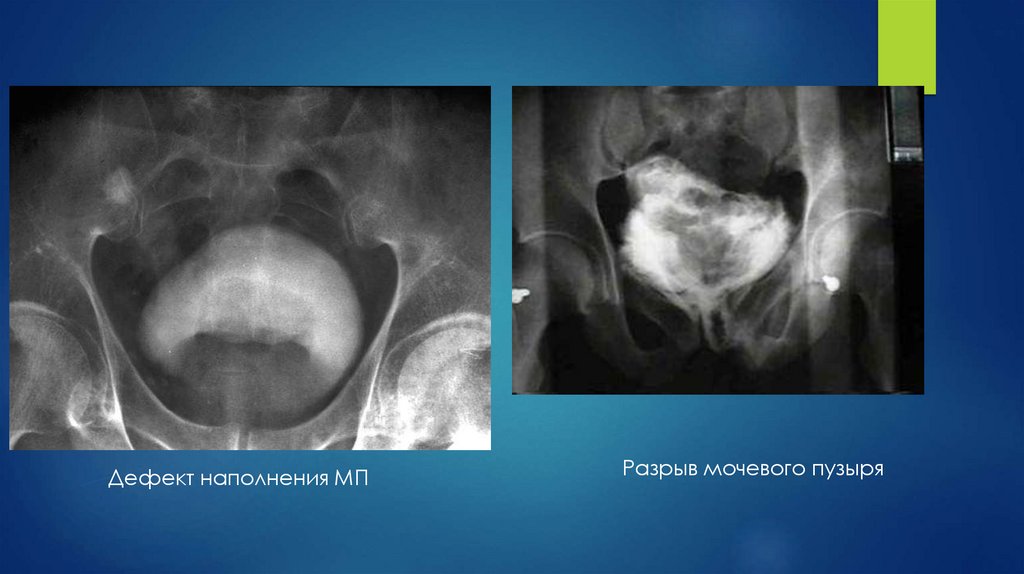

Дефект наполнения МП

Разрыв мочевого пузыря